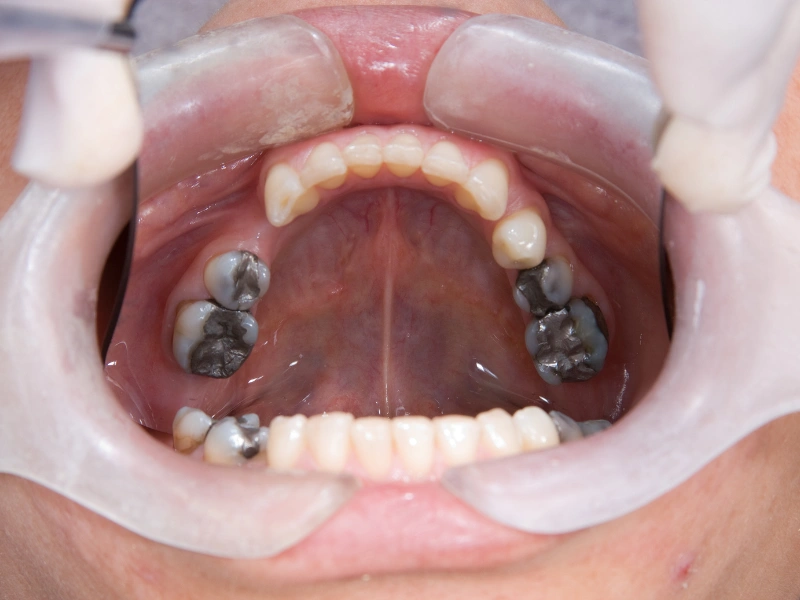

Atención integral en salud oral para toda la familia: desde controles de rutina hasta tratamientos de rehabilitación, estética y ortodoncia, en un mismo lugar.

Odontología integral Diagnóstico digital y preciso Enfoque preventivo y estético

Cuidamos tu salud oral en cada etapa

Especialidades dentales